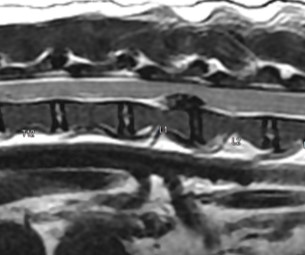

MRI의 경우 특히 뇌와 척수의 신경계와 같은 연부조직의 영상화에 특화되어 있어 다른 영상 기법보다 뛰어난 해상도를 나타냅니다.

- 디스크 질환

- 척수 질환

- 척추 골절

디스크질환 -